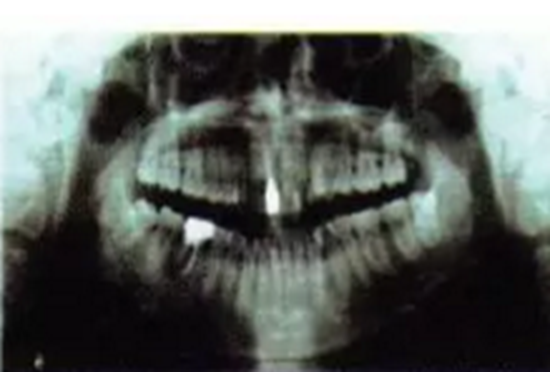

曲面全景片可見1為樁核冠、根尖1/3欠充,但未見陰影。1根方見多生牙高密度影。6遠中根外吸收、根管欠充,根尖周圍可見透射陰影,牙周膜增寬。上前牙及63近遠中牙槽骨度輕度水平吸收。1牙根尖片見其牙周膜清晰度尚可,未見根骨粘連。頭顱側(cè)位片測量結(jié)果示患者為I類、均角骨面型,上前牙和下前牙唇傾度減小(圖3)。

圖3術(shù)前曲面全景片